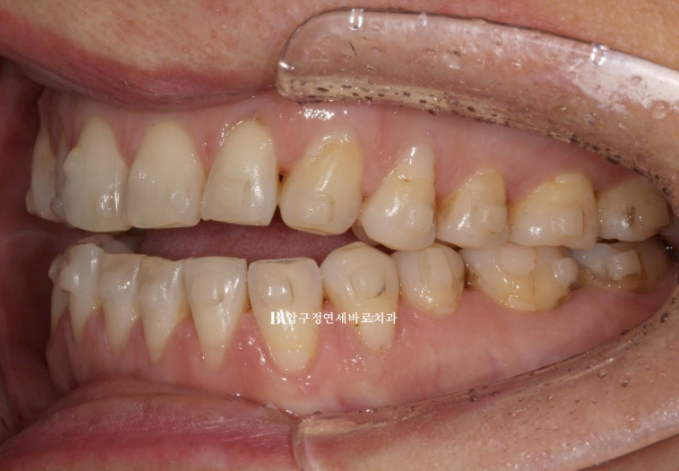

23.05~23.12

첫번째 작은어금니까지 8개 치아는 떠있고 두번째 작은어금니부터 큰어금니까지 3개씩 닿아있는 상태입니다.

이런 상태에서는 닿고있는 위 어금니 3개씩 총 6개 치아를 함입시키는 치료계획으로 진행합니다.

7개월에 걸쳐 1차세트 마무리 후 추가장치를 이해 리파인먼트 재제작에 들어갔습니다.